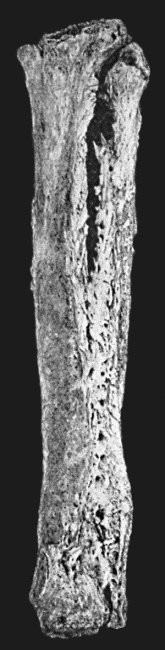

78 19.Tibia and Fibula, showing changes due to Chronic Ulcer of Leg

444 119.Femur and Tibia showing results of Acute Osteomyelitis

456 125.Tuberculous Disease of Tibia

457 126.Diffuse Tuberculous Osteomyelitis of Right Tibia